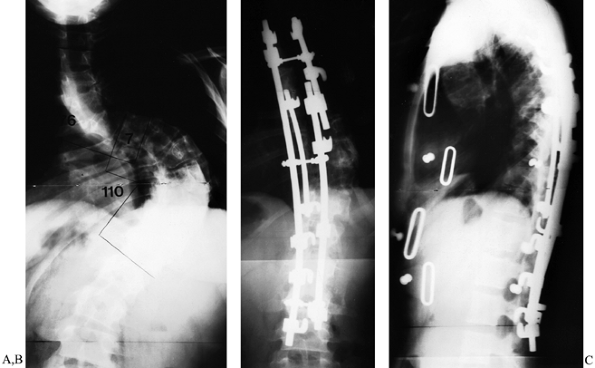

convex rod (Fig. 159.7).

Figure 159.7. A 28-year-old woman with a stiff King-type V thoracic scoliosis. A:

Preoperative PA radiograph demonstrates double thoracic curve. Upper

curve (apex T-5) measured 76°. Lower curve (apex T-10–T-11) measured

110°. B: Following right anterior thoracic

release, a short, apical distraction rod used to correct the uppermost

curve. A longer rod spanning the convexity of the lower thoracic curve

was connected to the first rod in bayonet fashion with a double-barrel

“domino.” Both these rods combine to make the third member of a

triple-rod construct using a short reduction rod at the apex of the

lower thoracic curve. C: Lateral view shows restoration of thoracic kyphosis and neutral thoracolumbar alignment. -